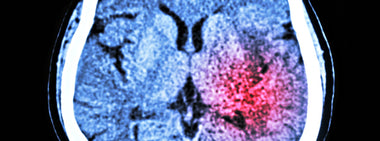

“Remember … Only YOU can prevent strokes.”

Do you recall the old Smokey the Bear ads about preventing forest fires? The Smokey campaign, created in 1944, focused...